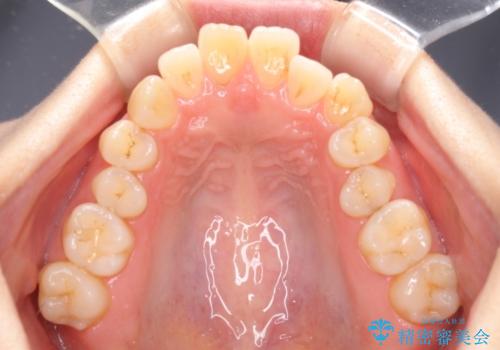

- 上の前歯の飛び出した感じを改善したいとのことで来院された患者様です。

上顎左右第一小臼歯2本、下顎左右第二小臼歯2本を抜歯し、ワイヤー装置にて口元を引っ込めるよう矯正治療を行うこととしました。

上下の前歯に隙間が空くほど上顎前歯が前に飛び出していましたが、抜歯矯正により上下前歯がぴったりと付くほど口元を引っ込めることができました。